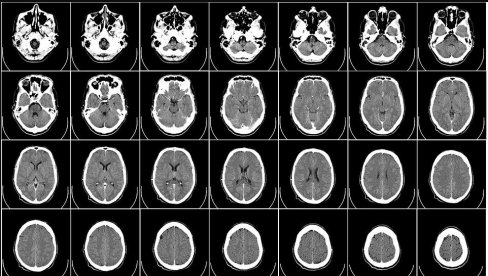

IPAK NISU "KAO BILJKE"? Novo istraživanje - I ljudi u komi imaju određeni nivo svesti

NOVO istraživanje sugeriše da svaki četvrti pacijent za kog se smatra da nema moždanu aktivnost nakon ozbiljnih povreda mozga, zapravo može da zadrži određeni nivo svesti.